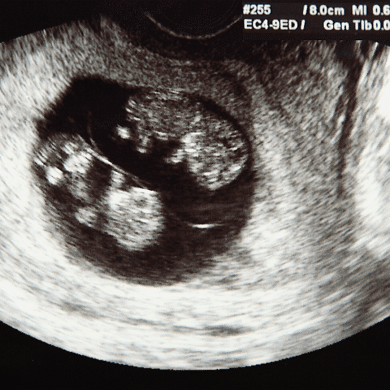

Twins can be seen on ultrasound as early as 6 or 7 weeks into the pregnancy. That’s great news since speculation doesn’t confirm a twin pregnancy and many pregnant women recall having a feeling before their twin pregnancy was confirmed. At least you don’t have to wonder for too long these days!

Can twins be seen on 6 week ultrasound?

This is one of the most common questions pregnant women ask when they are wondering about carrying twins early in their pregnancy. Usually, a second fetus can be seen at 6 weeks in the case of a twins ultrasound. That does NOT mean always. 6 weeks is still pretty early and a twin can be missed. Another reason all these scans and prenatal appointments are so critical to the health of you and your pregnancy!